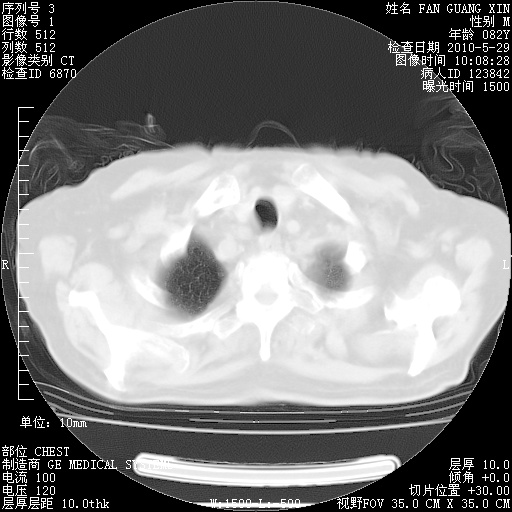

再治疗10天后的肺部CT